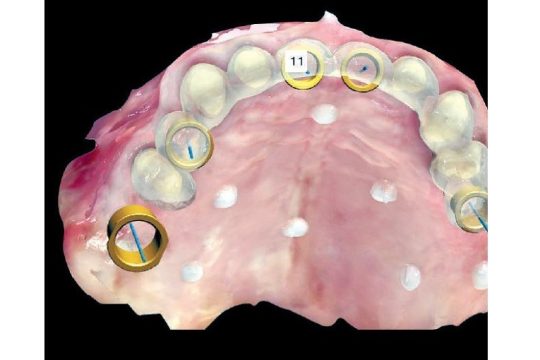

Digital Dentistry

The Full Digital Workflow in implant and Restorative Dentistry